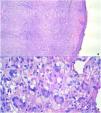

Procedimos a extirpar completamente el tumor. El estudio histopatológico identificó una proliferación dérmica nodular con histiocitos xantomizados, células gigantes multinucleadas de tipo cuerpo extraño y células multinucleadas de Touton, junto con linfocitos dispersos, células plasmáticas y eosinófilos (fig. 3a y b). La prueba inmunohistoquímica apuntó cepas positivas de CD68, no existiendo S100 y CD1a. El análisis de mutaciones BRAF-V600E mediante reacción en cadena de la polimerasa (PCR) a tiempo real resultó negativo. Las pruebas de laboratorio no revelaron anomalías en los parámetros rutinarios de los análisis de sangre, niveles de triglicéridos, función hepática o función renal. Las pruebas confirmaron el diagnóstico de xantogranuloma del adulto, produciéndose mejora clínica tras la extirpación quirúrgica. La paciente mantiene seguimiento dermatológico sin recidiva de la lesión.

La confirmación diagnóstica se realiza mediante biopsia cutánea. El análisis histopatológico identifica infiltrado histiocítico dérmico denso y células gigantes de Touton, que son células multinucleadas, con un centro citoplasmático eosinofílico homogéneo y xantomización periférica3.